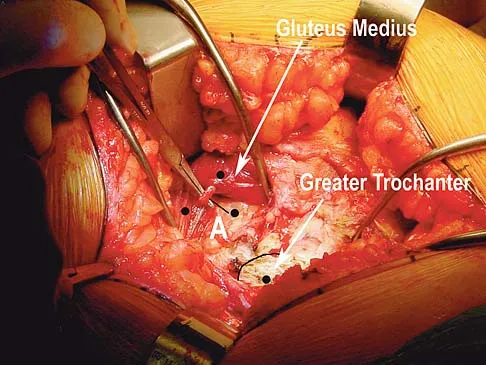

Question 77

A direct lateral (Hardinge) approach is used during total hip arthroplasty. The structure labeled A in Figure 7 is the

Explanation